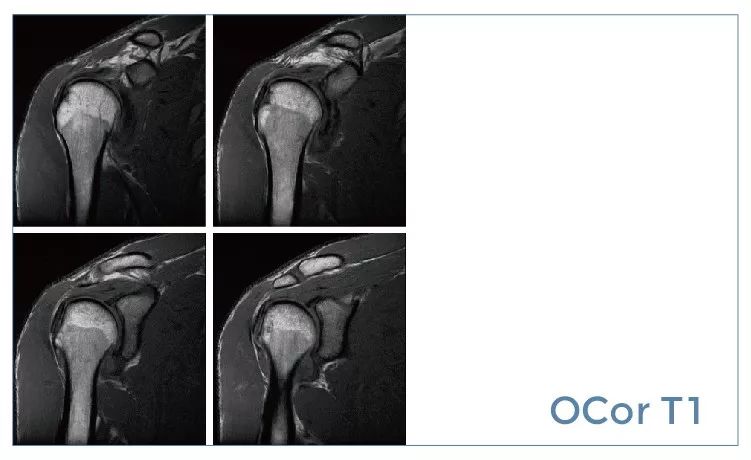

【朗润影像档案】磁共振影像病例分享(编号20190927)